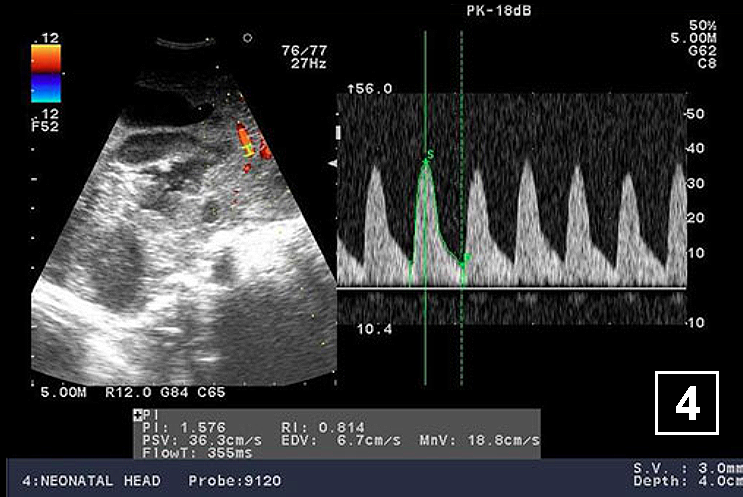

Neonatology Hydrocephalus Doppler 4 Image